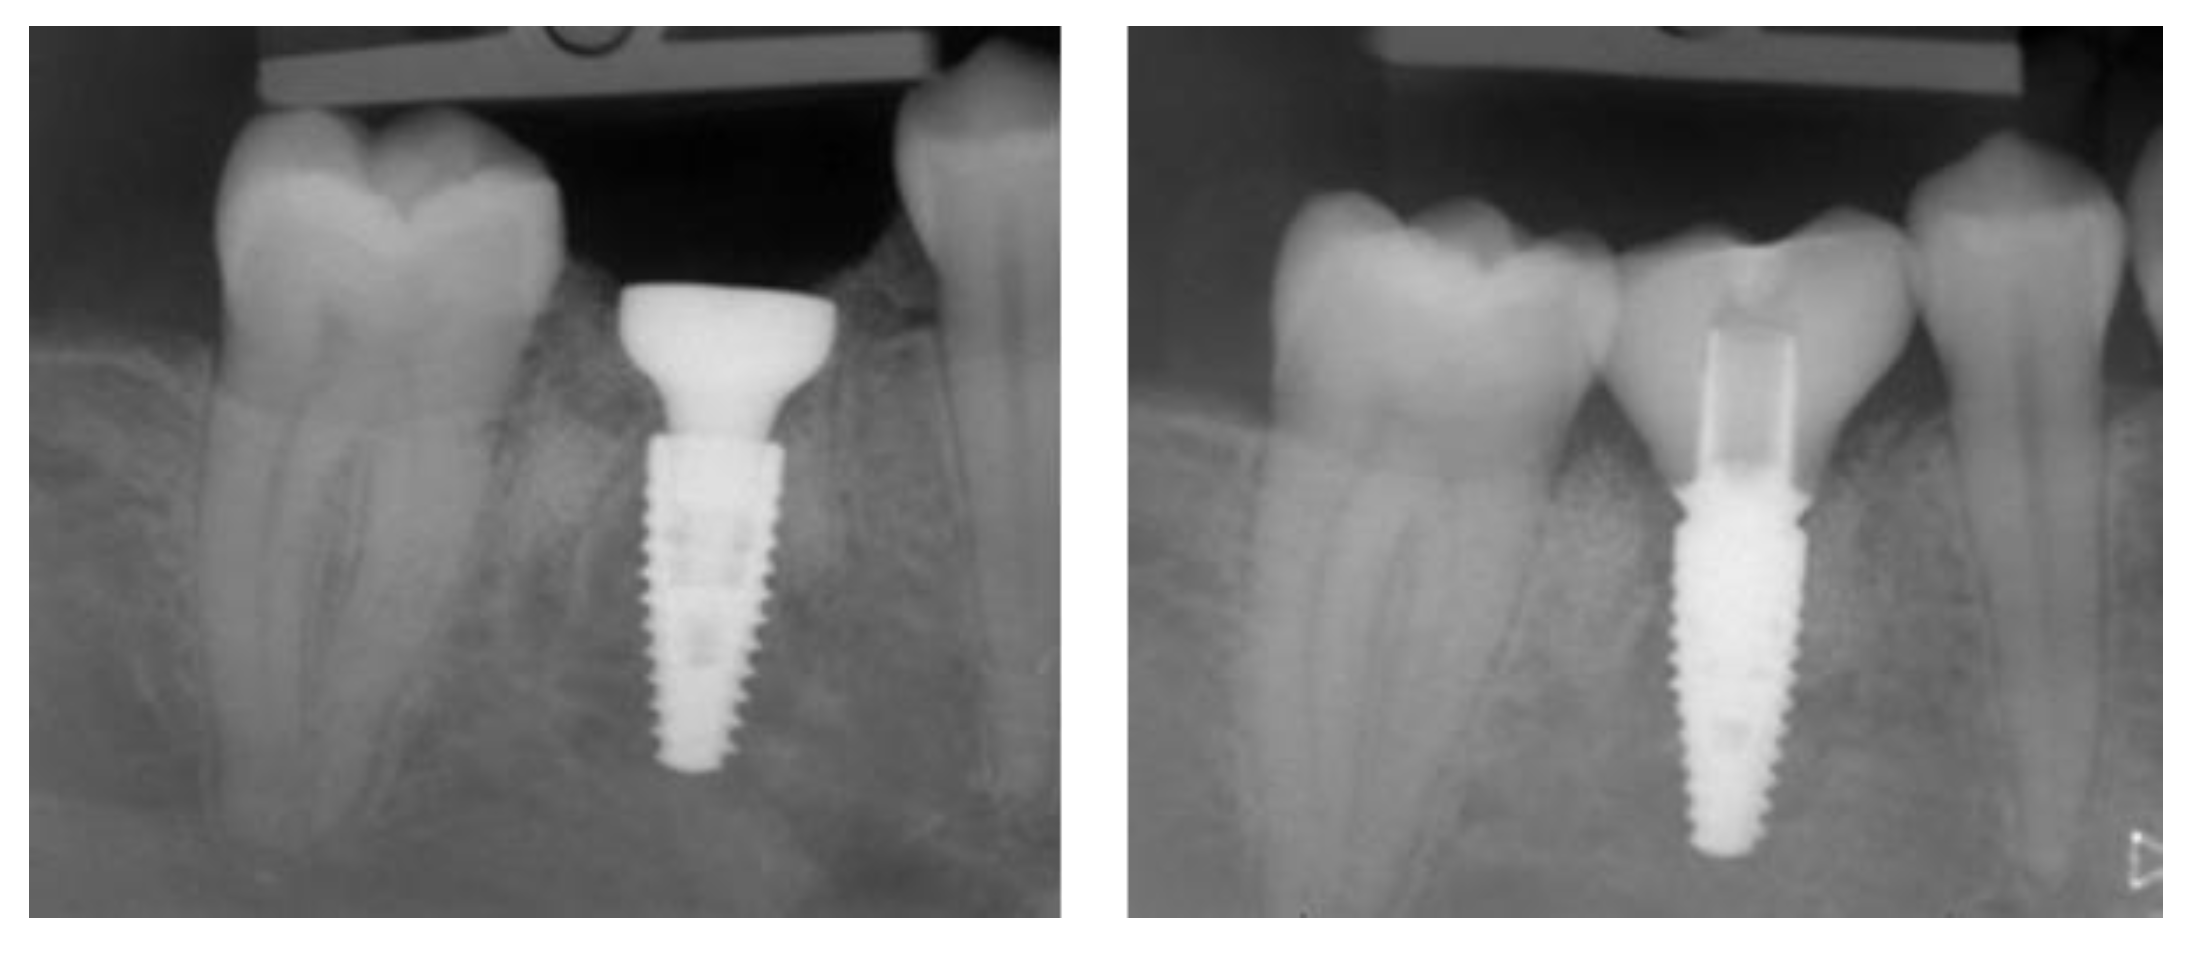

2.4.1. Radiographic Measurements

3.2. Marginal Bone Level Outcomes

| Mesial Marginal Bone Level (2D) [mm] after Immediate Placement | ||||||||

|---|---|---|---|---|---|---|---|---|

| Patient | 1 | 2 | 3 | 4 | 5 | Median | IQR | |

| Implant position | 45 | 35 | 45 | 45 | 13 | 23 | NA | NA |

| Post-OP mesial | 1.8 | 0.0 | 0.1 | 3.0 | 0.4 | 0.4 | 0.4 | 0.18–1.45 |

| 1 year mesial | 0.6 | 0.0 | 0.1 | 1.5 | 0.1 | 0.1 | 0.1 | 0.1–0.48 |

| Post-OP distal | 1.2 | 0.0 | 0.1 | 3.0 | 0.4 | 0.4 | 0.4 | 0.18–1.0 |

| 1 year distal | 0.6 | 0.0 | 0.1 | 1.5 | 0.2 | 0.0 | 0.2 | 0.03–0.5 |

| Marginal Bone Level (2D) [mm] after Delayed Placement | ||||||||

| Implant position | 35 | 45 | 35 | 35 | 35 | 45 | NA | NA |

| Post-OP mesial | 2.0 | 1.0 | 0.2 | 0.6 | 0.2 | 0.2 | 0.4 | 0.2–0.9 |

| 1 year mesial | 1.6 | 0.5 | 0.0 | 0.3 | 0.1 | 0.1 | 0.3 | 0.1–0.45 |

| Post-OP distal | 0.0 | 0.5 | 0.0 | 0.6 | 0.1 | 0.1 | 0.1 | 0.03–0.4 |

| 1 year distal | 0.0 | 0.2 | 0.0 | 0.3 | 0.1 | 0.1 | 0.1 | 0.03–0.18 |